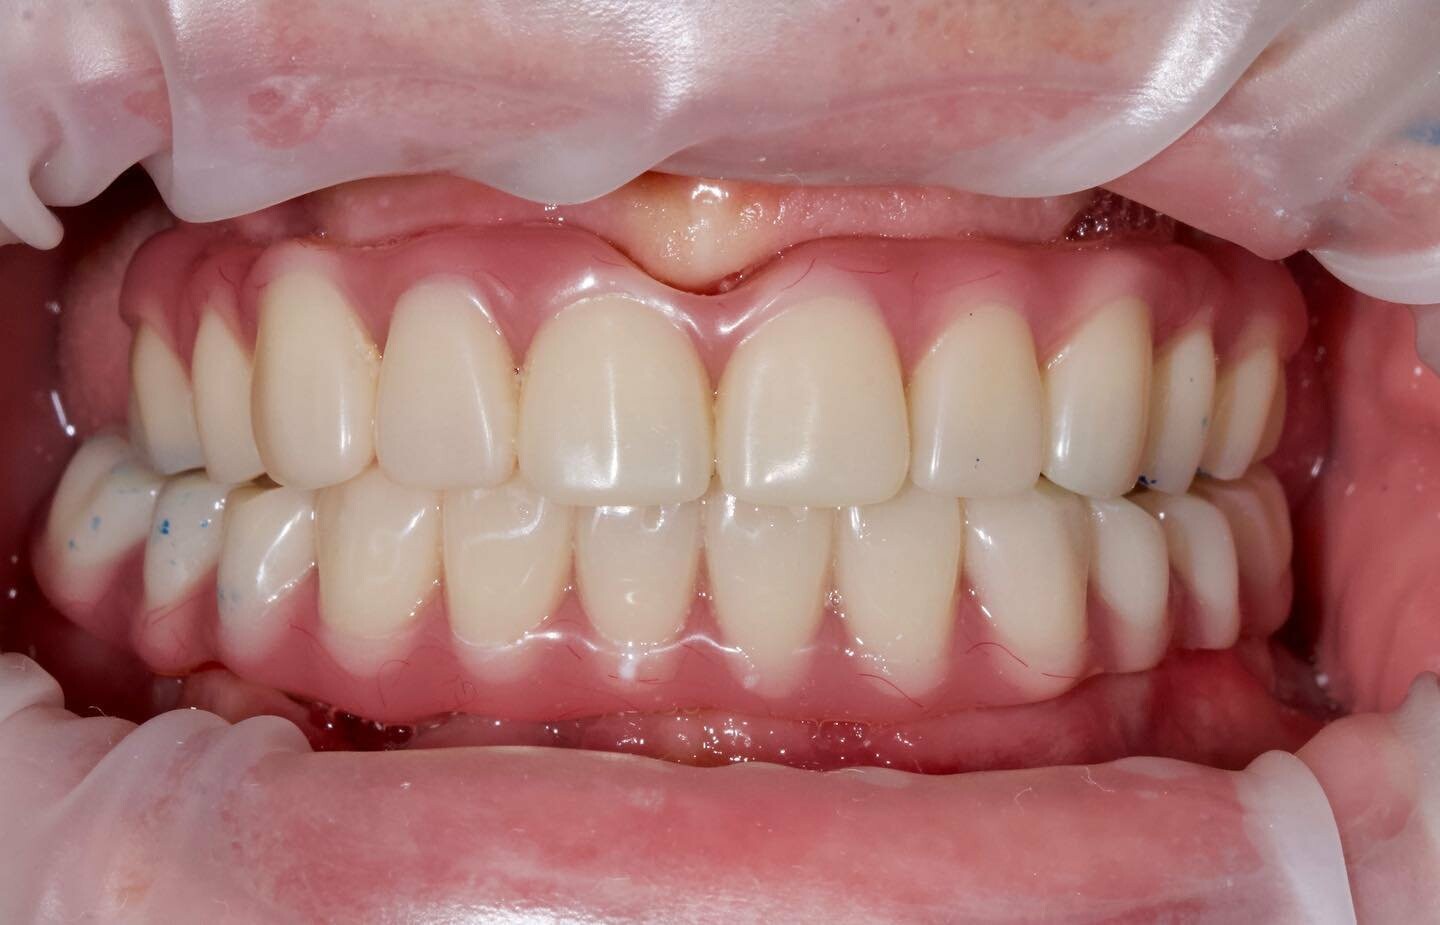

Временные конструкции пациента с генерализованный пародонтитом с применением методики All-on-4 (все на 4-х)

Врач @motordantist